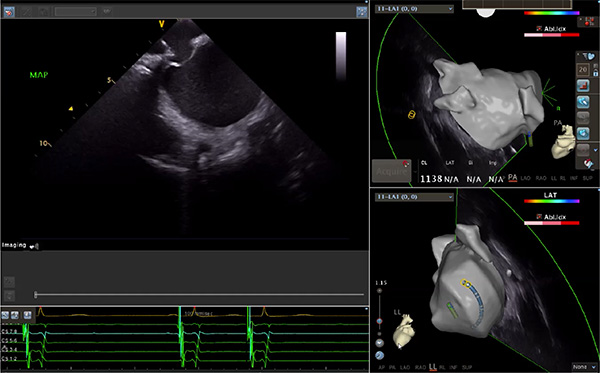

超聲心動圖技術(shù)包括常規(guī)經(jīng)胸超聲(TTE)、經(jīng)食管超聲(TEE)、心腔內(nèi)超聲(ICE)、超聲聲學(xué)造影(MCE)、三維超聲心動圖等,ICE是一種新興技術(shù)——將微型的換能器安裝在心導(dǎo)管的尖端,經(jīng)由外周血管輸送至心腔內(nèi)部,換能器發(fā)射聲波,對心臟及其鄰近組織進(jìn)行實時高質(zhì)量成像和(或)血流動力學(xué)測定的超聲成像技術(shù)。基于不同的技術(shù)原理,心腔內(nèi)超聲導(dǎo)管被分為兩類:機(jī)械旋轉(zhuǎn)式超聲導(dǎo)管和相控陣超聲導(dǎo)管。目前,臨床上主要應(yīng)用的是相控陣超聲導(dǎo)管,ICE成像通過術(shù)者旋轉(zhuǎn)導(dǎo)管及操縱導(dǎo)管手柄上的兩個旋鈕來完成。

ICE門檻高、集成了超聲和圖像處理最前端的技術(shù),是當(dāng)前內(nèi)窺超聲方向最挑戰(zhàn)的領(lǐng)域。不同于傳統(tǒng)接觸式三維重建方法會產(chǎn)生假腔,影響術(shù)者對靶點或結(jié)構(gòu)的判斷,心腔內(nèi)超聲(ICE)可直接顯示心臟結(jié)構(gòu),有助于理解心臟內(nèi)各部位之間的解剖關(guān)系,不僅具有實時成像、并發(fā)癥監(jiān)測以及良好的耐受性,同時以股靜脈入路,無需全麻或深度鎮(zhèn)靜,日益成為心臟介入手術(shù)中重要輔助工具,被譽為心臟介入醫(yī)生的“黃金眼”。心腔內(nèi)超聲可用于多種心臟介入手術(shù),潛在患者群體龐大,動脈網(wǎng)測算我國心腔內(nèi)超聲導(dǎo)管市場空間或?qū)⒊?00億元,具有廣闊前景。

隨著心腔內(nèi)超聲的應(yīng)用更廣,性能也在逐漸優(yōu)化,已從二維成像轉(zhuǎn)變?yōu)?strong>三維成像,極大增強(qiáng)了引導(dǎo)及可視化能力。二維心腔內(nèi)超聲支持雙平面或三平面成像,可顯示兩個或三個不同的平面視圖,但醫(yī)生需將這些圖像在腦海中重新構(gòu)建為三維解剖結(jié)構(gòu)。三維心腔內(nèi)超聲則可直接呈現(xiàn)三維解剖結(jié)構(gòu)圖,便于醫(yī)生更輕松地開展手術(shù)。按照產(chǎn)品發(fā)展方向,預(yù)計心腔內(nèi)超聲還將向更清晰、精準(zhǔn)、多功能等方向發(fā)展。